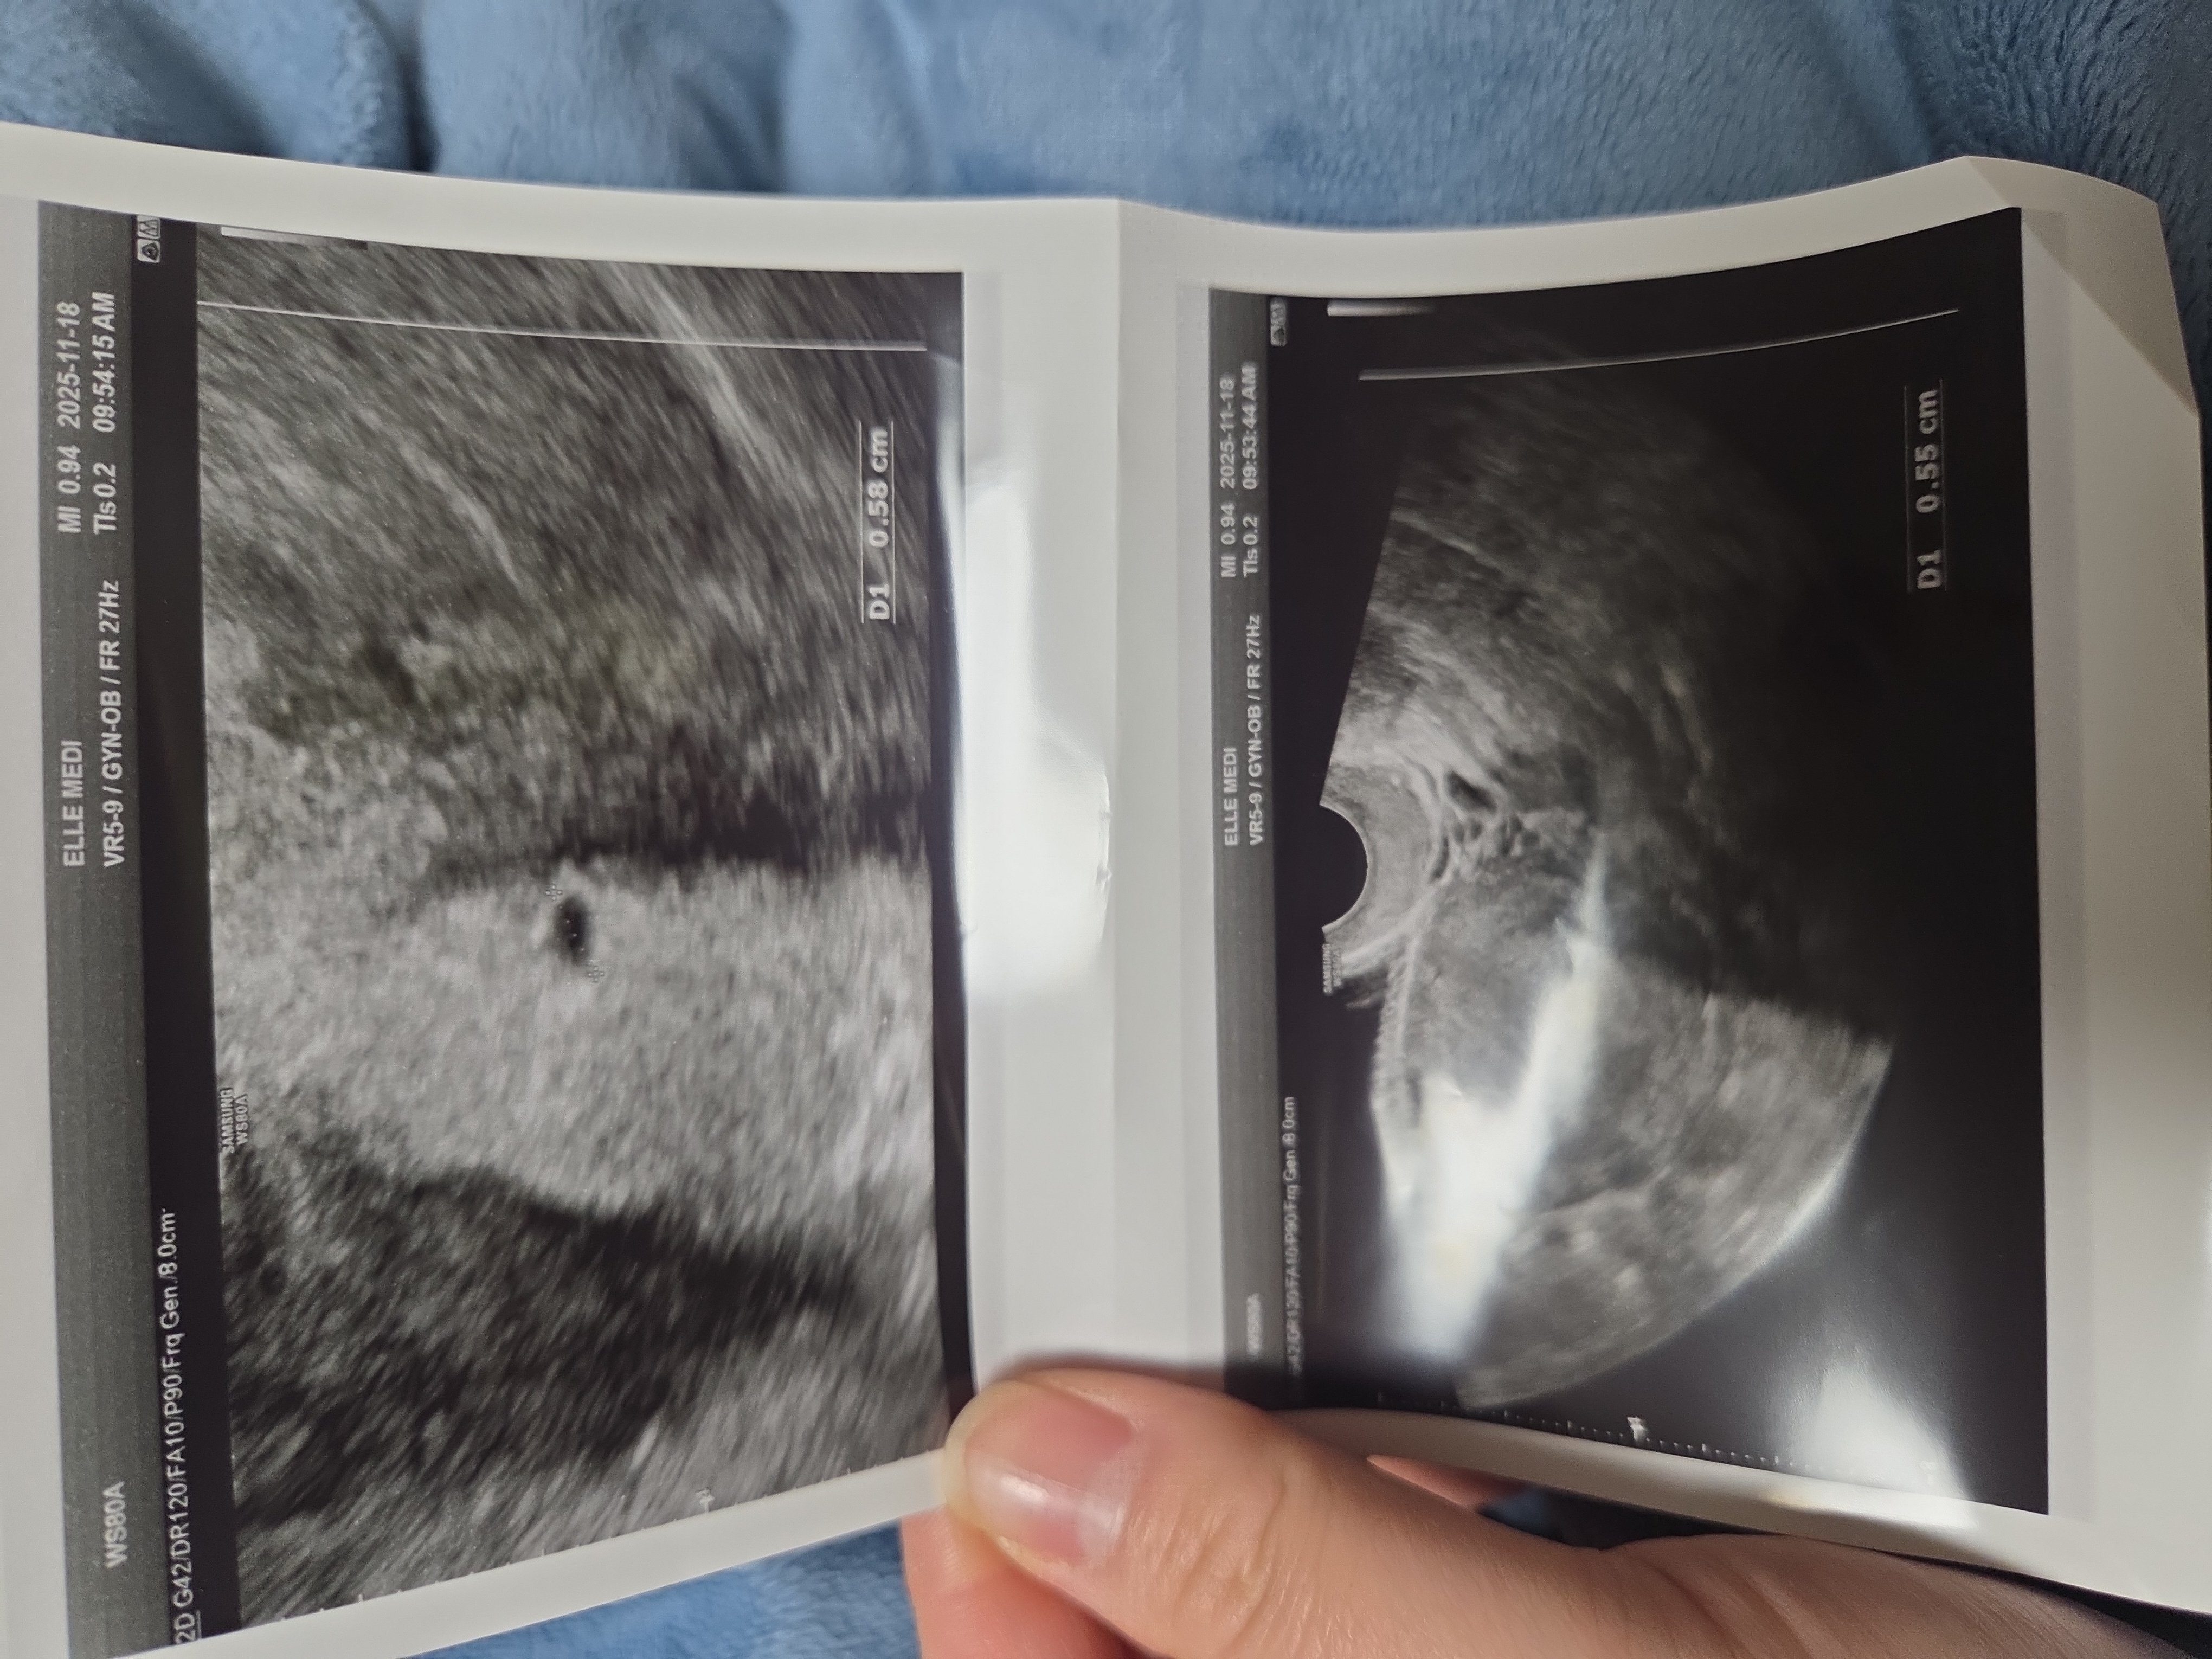

초음파사진봐주세요 ㅠ

5주차때 찍은건데 크기가 너무 작은것같아요 원래 크기가 이런가요???ㅠㅠ 불안해요 계류유산해본적이 있어서 그런지..이시기엔 원래 그런건지 봐주세요 ㅠ 난황 보이는 사람도 잇다고하는데 전 안보이네요 ㅜ